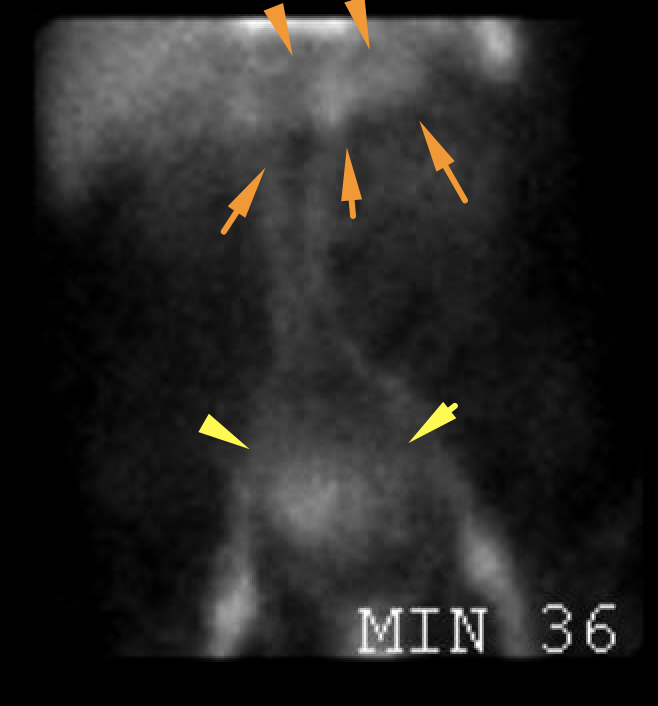

Age: 89

Sex: Male

Indication: GI bleeding

Radiotracer: Tc99m labeled RBCs

Sample ReportNo evidence of active GI bleeding during the course of this study.